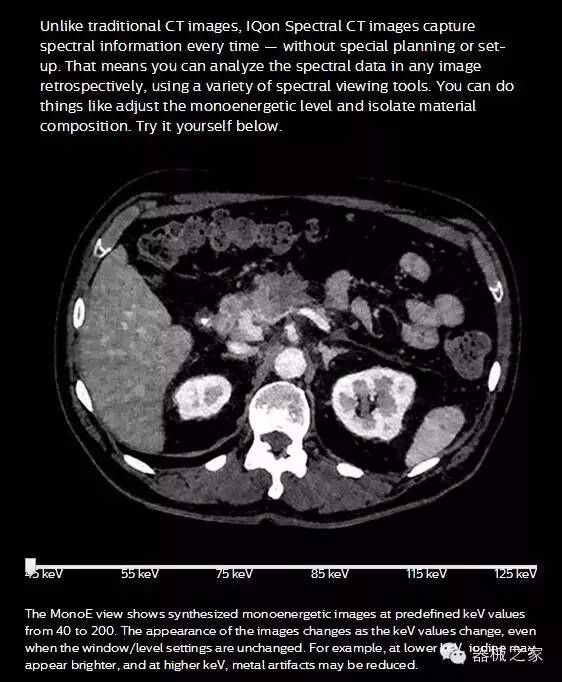

IQon光譜CT能夠按照需求提供光譜量化和工具,并能通過簡單工作流程、在低劑量下對結(jié)構(gòu)進行定性分析

IQon光譜CT -- 是業(yè)界首臺以探測器為成像基礎(chǔ)的光譜CT,它可以在單次常規(guī)掃描下獲得傳統(tǒng)解剖影像及光譜功能影像。不僅可以提供精準的診斷信息,還可簡化工作流程、在低劑量下完成定量與定性分析。